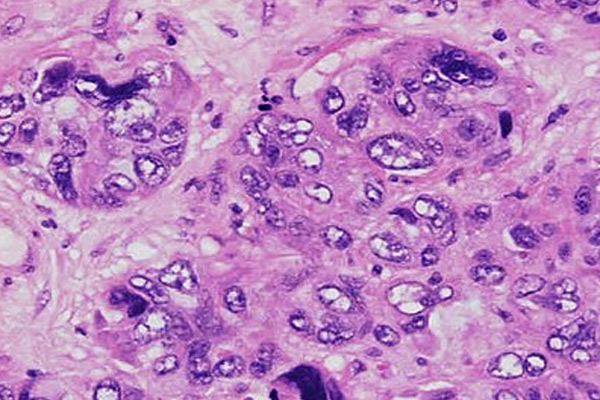

Μετά την αποφοίτησή μου ετάχθην σε ερευνητικό πρόγραμμα του ανωτέρω Πανεπιστημίου υπό την επίβλεψη του καθηγητή Πανεπιστημίου Παθολογικής Ανατομικής Dezso Balazs, ο οποίος επέβλεψε και κατηύθυνε την έρευνά μου. Το σχέδιο έρευνας που κατέθεσα αξιολογήθηκε από τη Feichtinger Foundation με συνακόλουθη απόφαση για χρηματοδότηση του μέχρι ολοκλήρωσης του, απόφαση ιδιαιτέρως τιμητική για μένα.